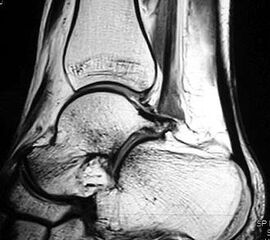

Z.n. Distorsion des Fußes mit „Ruptur“ der (vorbestehenden) talocalcanearen Coalitio. Die Wassereinlagerung in den an die Coalitio angrenzenden knöchernen Bezirken ist im MRT gut zu erkennen. Nach monatelangen Beschwerden spontane Besserung.

MRT und CT konkurrieren in der Fein-Darstellung der Knochenbrücke, der Beurteilung der nichtbetroffenen Anteile des Subtalargelenkes und der Sekundärveränderungen. Das MRT bietet den Vorzug, bindegewebige und knorpelige Strukturen (Abb. 2) und bei Einsatz von Kontrastmittel auch knöcherne Aktivierungsphänomene genau abzubilden; die knöcherne Feinstruktur und genaue Ausdehnung dagegen ist mit dem Dünnschicht-CT wesentlich exakter darstellbar (Abb.3). In manchen Fällen ist eine 3-D-Rekonstruktion des CT hilfreich. Besonders wichtig ist eine geeignete Schichtebenen-Wahl:

Diagnostisch sollte neben Röntgenübersichtsaufnahmen (indirekte radiologische Zeichen: Dorsaler Traktions-Osteophyt am Taluskopf, „talar beaking“; kontinuierliche Linie der Trochlea-tali-Kontur übergehend in die Sustentaculum-tali-Kontur, „C-Zeichen“ (Abb. 11) 10) immer die dreidimensionale Bildgebung eingesetzt werden. Das MRT (mit Kontrastmittel) kann die Struktur der Brückenbildung und z.B. die Qualität des Restgelenkes (Knorpel-Dicke) besonders gut abbilden; das Dünnschicht-CT zeigt die knöcherne Feinstruktur im Bereich der Coalitio und den oft sehr schrägen Spalt-Verlauf im Frontalschnitt dagegen häufig genauer. Meist findet sich die Überbrückung im Bereich der medialen Facette; die Schichten sollten jedoch bis weit nach dorsal beurteilt werden, da ansonsten dorsomediale Formen übersehen werden können. Rozansky et al 7 unterschieden fünf morphologische Typen auf der Basis von 3-D-CT-Rekonstruktionen. Allerdings ist eine prognostische Zuordnung bisher nicht möglich.